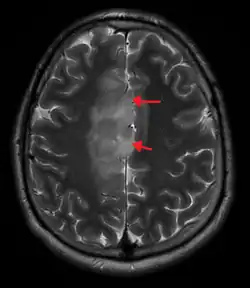

An X-ray computed tomography (CT) or magnetic resonance imaging (MRI) scan is necessary to characterize the anatomy of this tumor as to size, location, and its homogeneity and heterogeneity. However, final diagnosis of this tumor, like most tumors, relies on histopathologic examination (biopsy examination).[4]

If resected, the surgeon will remove as much of this tumor as possible without disturbing eloquent regions of the brain such as the speech–Broca's area and Wernicke's area–and motor cortexes and other critical brain structure. Thereafter, treatment may include chemotherapy and radiation therapy of doses and types ranging based upon the patient's needs. Subsequent MRI examination are often necessary to monitor the resection margin.